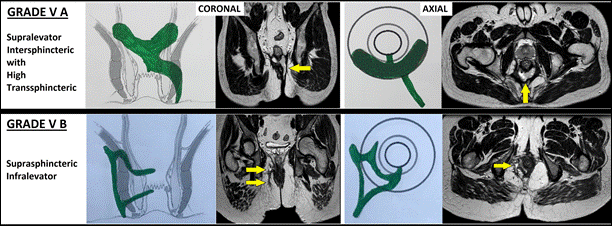

V |

Rò rất phức tạp: V-A:Rò xuyên cơ thắt ngoài mức cao kèm lan gian cơ thắt phía trên cơ nâng hậu môn (supralevator) V-B:Rò suprasphincteric (Rò vòng lên trên cơ thắt ngoài, rồi đi xuống lại, nhưng không vượt cơ nâng hậu môn) V-C:Rò ngoài cơ thắt hậu môn (extrasphincteric) (Đường rò không đi qua cơ thắt hậu môn mà xuất phát từ trực tràng hoặc sâu trong khoang chậu, sau đó lan xuống vùng quanh hậu môn) |